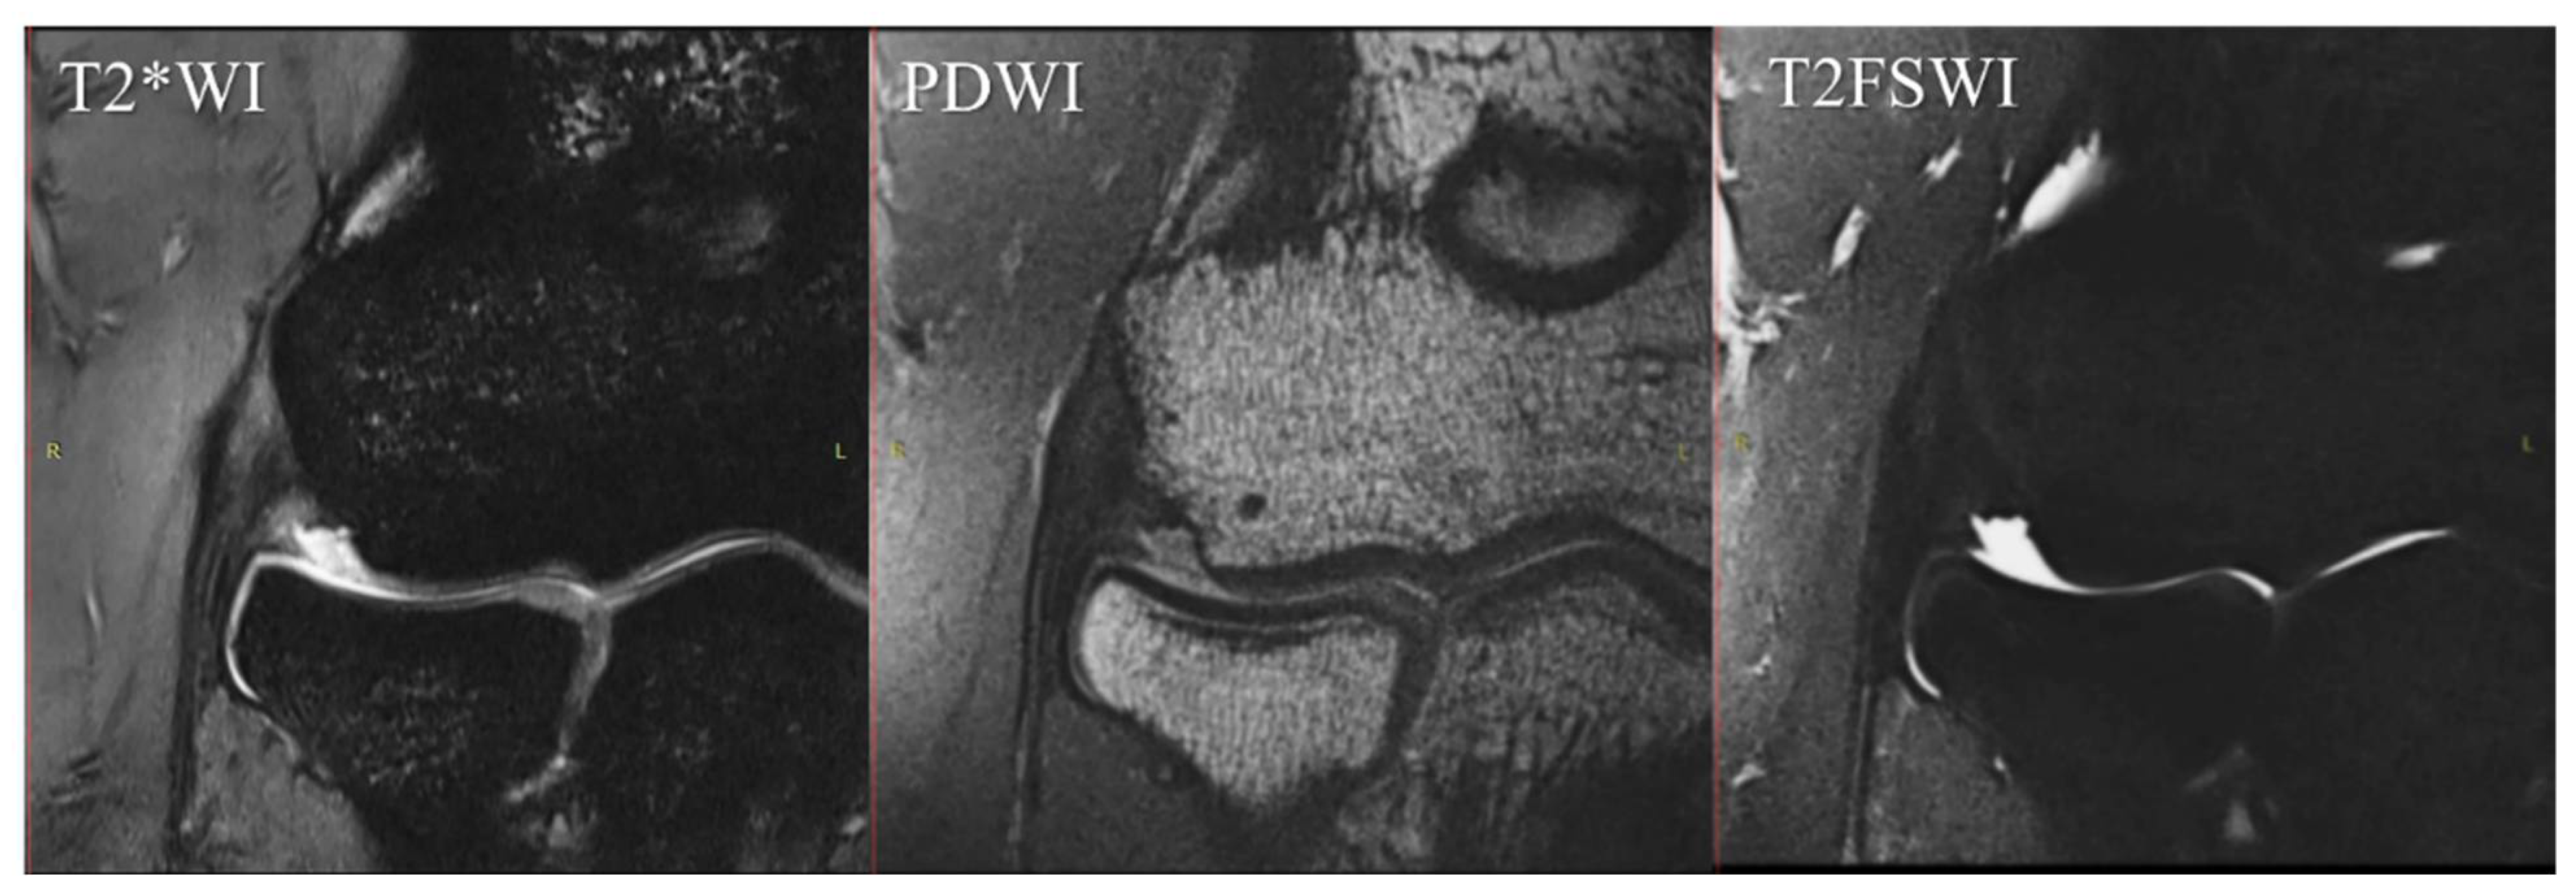

We chose T2FSWI for MRI scoring because PDWI and T2*WI had short echo times and may have overestimated the findings due to the magic-angle phenomenon (Figure 3) [27,28,29].

Figure 3.

Differences in signal intensity of the CET/LCL complex by sequence. The unaffected elbow of a 32-year-old male. These images are same-level slices of the MRI coronal section in each sequence. In this case, T2*WI shows a high signal at the CET/LCL complex despite a complete low signal in the sequence of PDWI and T2FSWI. MRI, magnetic resonance imaging; T2*WI, T2*-weighted images; PDWI, proton-density-weighted images; T2FSWI, T2 fat-saturated weighted images; CET, common extensor tendon; LCL, lateral collateral ligament.